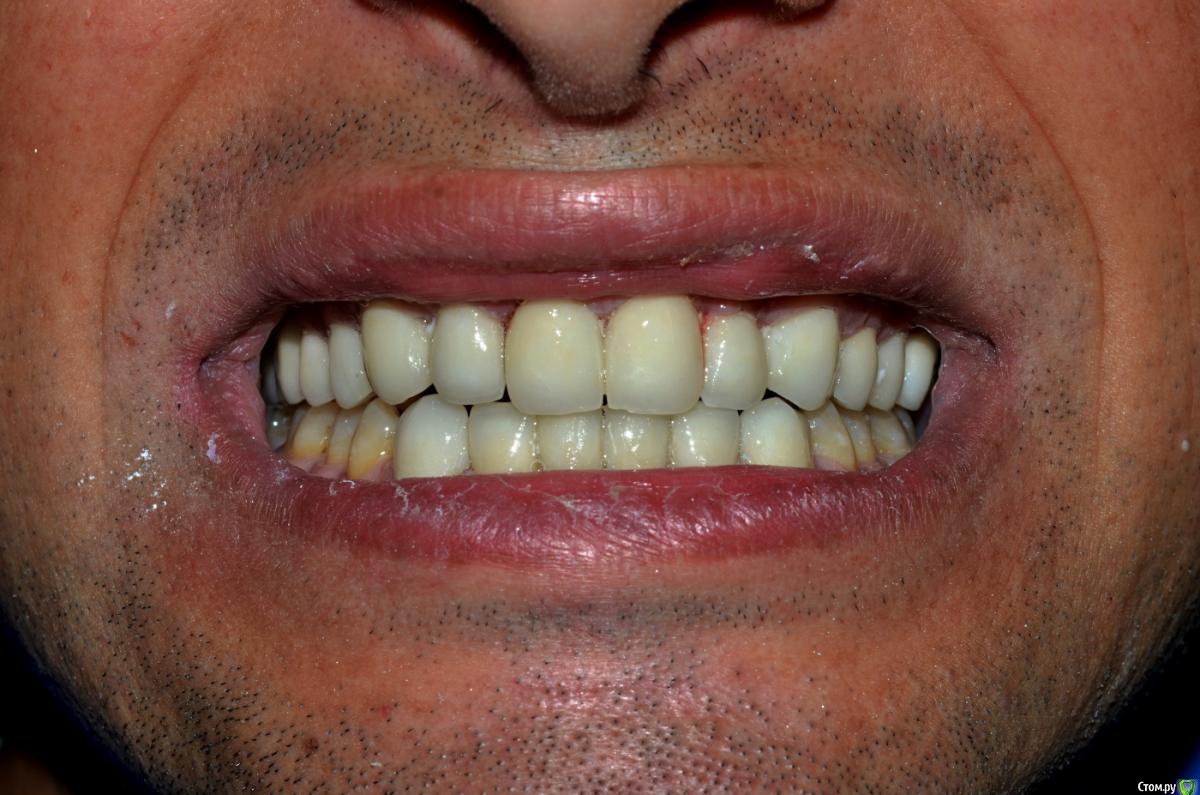

NazranDantist Опубликовано 4 сентября, 2015 Поделиться Опубликовано 4 сентября, 2015 К сожалению фото до где-то потерялись, были очень длинные клыки, смыкались по типу ножниц. Пришлось поднимать прикус на 0.6-0.8 мм. Обточка, времянки, слепки - 3 часа, фиксация 2 часа, без примерок на готово. Пациент попросил "ахпер, сделай две белый полосы, как на моем камаро" . Все циркон с вестибулярной облицовкой, фиксация Фуджи+. Фоткал пока цемент еще застывал.Учимся работать по китайскому протоколу, тотал за неделю и за 3000$ 1 1 Ссылка на комментарий

NazranDantist Опубликовано 4 сентября, 2015 Автор Поделиться Опубликовано 4 сентября, 2015 (изменено) Техник сделал все за 3 дня, сроки поджимали, к тому же пациент не требовал особых изысков и соответственно платил, главное белые и ровные))) Фото в первом сообщении немного засвечено. Цемент не убран на фото, через месяц приедет, еще раз сфоткаю с десной. Модели, слепки не фотографировал, был классический оттиск двухслойный с-силиконом. Кризис)) Изменено 4 сентября, 2015 пользователем NazranDantist Ссылка на комментарий

art700 Опубликовано 4 сентября, 2015 Поделиться Опубликовано 4 сентября, 2015 Десна смущает, хотя фото может такое и остатки цемента. С цветом опять, по фото может, но как выше писали разница видна. Ссылка на комментарий

NazranDantist Опубликовано 4 сентября, 2015 Автор Поделиться Опубликовано 4 сентября, 2015 Пациенту понравилось. Эстетика не супер, я ж говорю, делалось за три дня и за ограниченный бюджет, в 18:00 - достали из печки после глазури, в 21:00 пациент уехал (час на транспортировку работы), еще не дорос до того уровня, чтоб выбирать пациентов . С десной все ок, фото препа - перед фиксацией (можете обратить внимание на десну), фото после - только, только цемент начал стыть. Перед этой работой читал про то, как наши граждане ездят в китай лечить зубы, и все думал, как это за 3-5 дней там делают тоталы. Теперь я это знаю . 1 Ссылка на комментарий